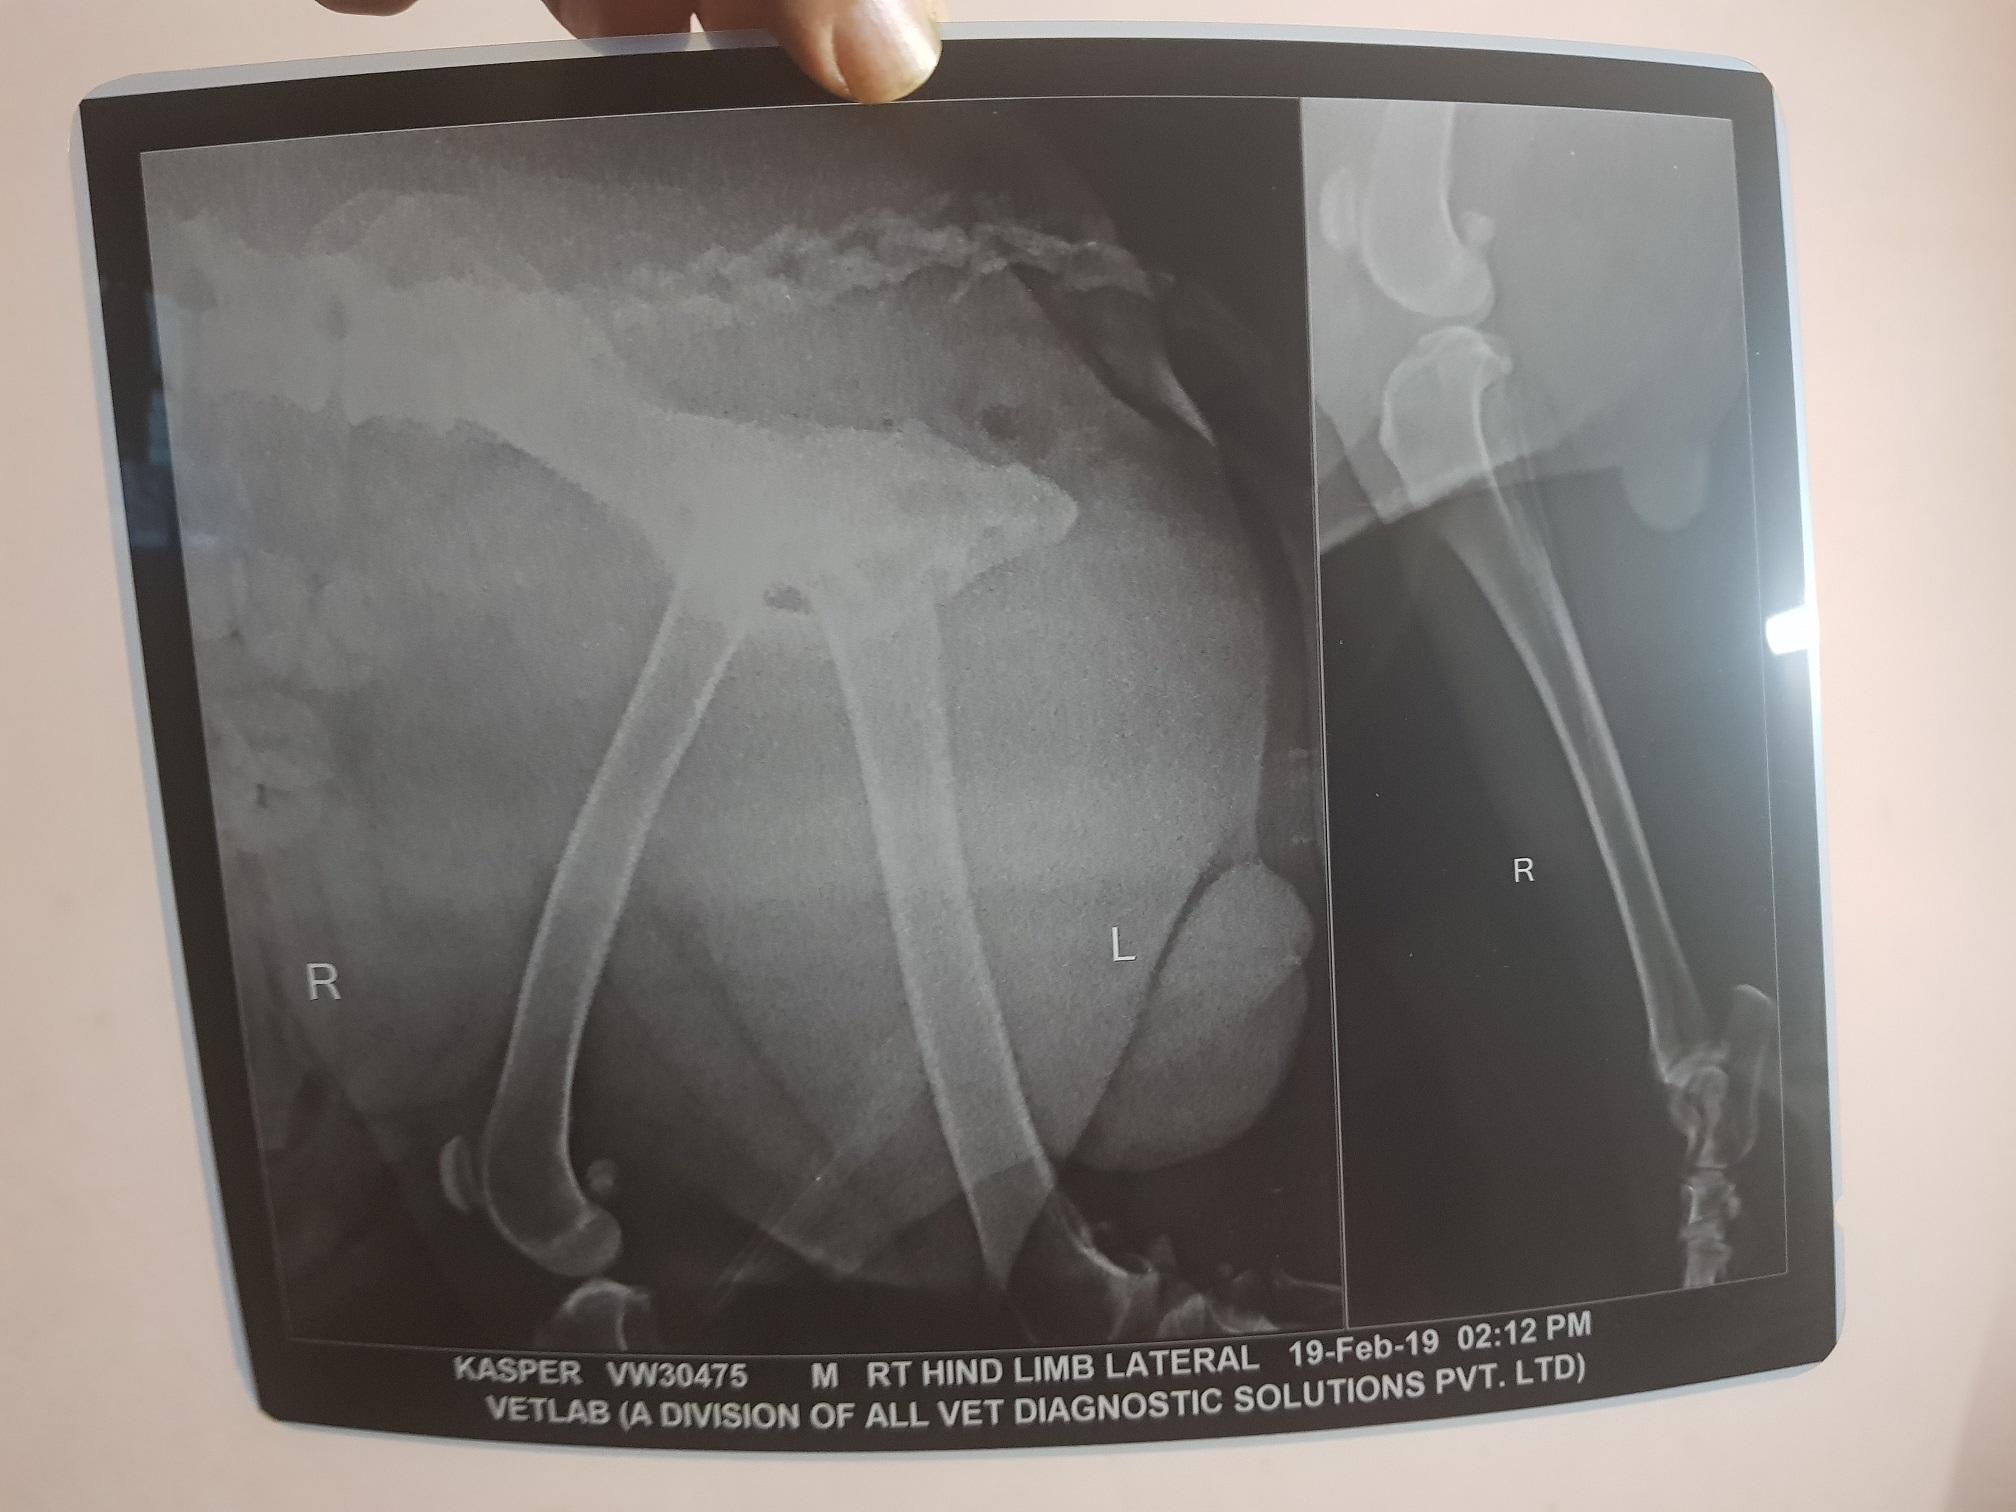

My rottweiler dog leg shaking. i am attaching the Xray report. kindly tell me what should i do ? please tell me the medicine for my pet :(

Hello. Kasper has evidence of hip dysplasia. It is not severe, but enough to cause your pet some discomfort. We routinely see these type of changes, especially in the larger breed dogs. Treatment includes the use of pain medications, joint supplements, weight loss, & consistent, but easy exercising. Pain meds include NSAIDs such as carprofen, Previcox, Deramax & Meloxicam, additional pain relief such as Tramadol &/or Gabapentin, & joint supplements such as glucosamine/chondroitin sulfate, Adequan injections & ocassionally omega 3 fatty acids. Thanks for using Petco Pet Education Center, formerly Petcoach.